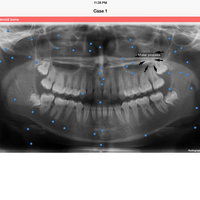

iPanoramic

Panoramic radiographs provide a quick overview of the patient’s teeth, jaws, and bone. This is useful for diagnoses and treatment planning.

The app provides dental students and dental hygiene an easy and fun way to master different anatomical landmarks. Dental practitioners can use the app to refresh their knowledge about panoramic radiographs. The app can be used a quick reference when needed. It's fully interactive and allows knowledge assessment through a quiz mode.